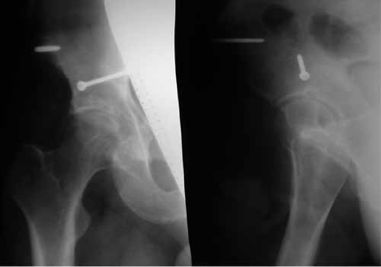

Рентгенография тазобедренного сустава в двух проекциях (прямая и аксиальная). Срок после оперативного лечения — 6 лет

Большая, средняя и малая ягодичные мышцы вместе с грушевидной отводятся кверху, верхняя близнецовая — книзу. Следует помнить о выходе из малого таза седалищного нерва под грушевидной мышцей в проксимальном ее участке. Также производится ревизия состояния хряща головки бедренной кости, отломка, установка его после промывания полости сустава, стабильная фиксация с элементами компрессии (рис. 5, 6).

Обзорная рентгенограмма таза. Состояние после открытой репозиции и фиксации среднего отдела заднего края вертлужной впадины 2 винтом. Стабилизация и разгрузка тазобедренного сустава в аппарате внешней фиксации

Рентгенография тазобедренного сустава в двух проекциях (прямая и аксиальная). Срок после оперативного лечения — 3 года